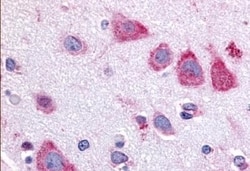

TAOK1 Polyclonal Antibody for IHC (P)

| Immunohistochemistry (Paraffin) | |

| Synthetic 16 amino acid peptide from internal region of human TAOK1. | |